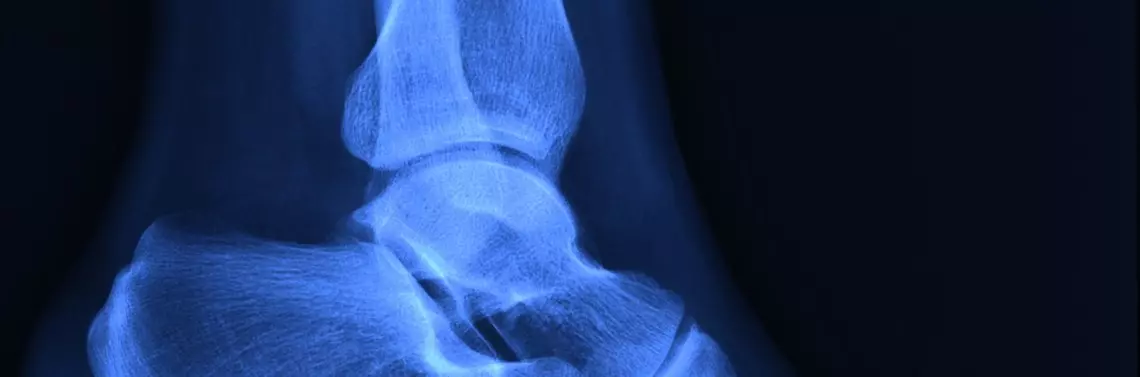

Diagnostyka złamania opiera się głównie na wykonaniu oceny radiologicznej. Zazwyczaj wykonuje się zdjęcie rentgenograficzne (RTG) w dwóch projekcjach – przednio-tylnej lub tylno-przedniej, bocznej lub osiowej. Dodatkowo w przypadku uszkodzenia tkanek miękkich przeprowadza się badanie ultrasonograficzne (USG), tomografię komputerową (TK) czy też rezonans magnetyczny (RM) lub badanie artroskopowe3 4.